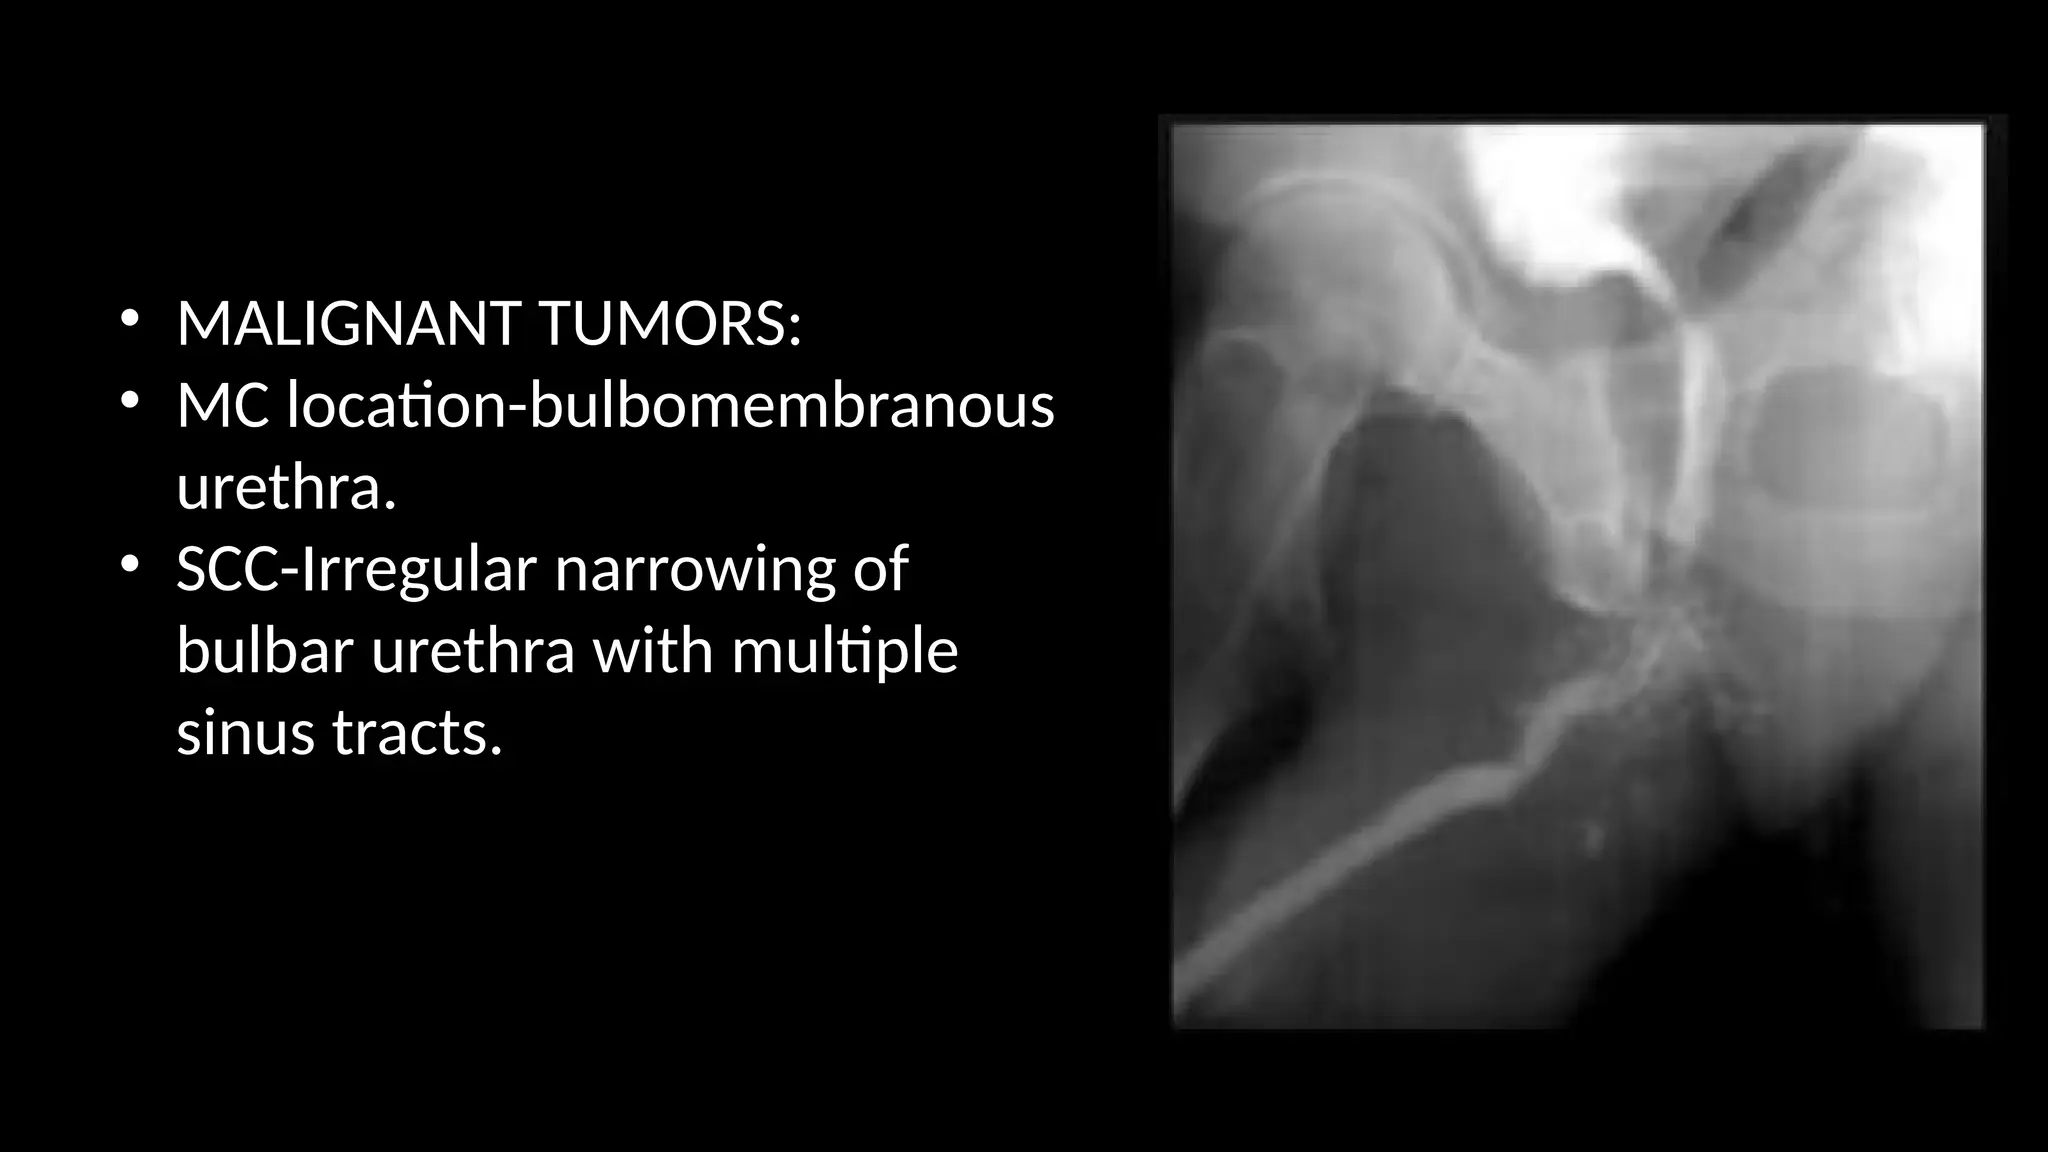

• MALIGNANT TUMORS:

• MC location-bulbomembranous

urethra.

• SCC-Irregular narrowing of

bulbar urethra with multiple

sinus tracts.

• MALIGNANT TUMORS: •MC location-bulbomembranous urethra. • SCC-Irregular narrowing of bulbar urethra with multiple sinus tracts.